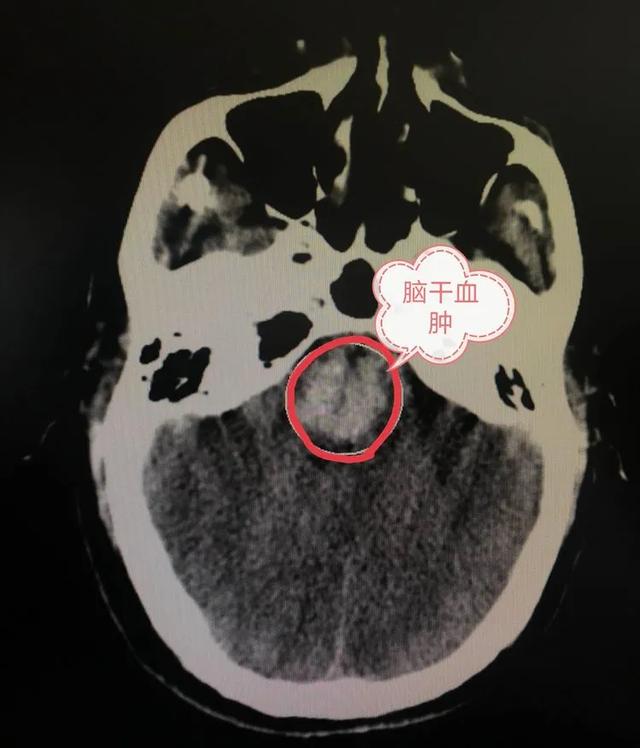

到达医院急诊科时,万某已经完全丧失意识、大小便失禁、呼之不应,立即打开急诊绿色通道,急查头颅CT显示脑干大量出血,出血量超过10ml,(脑干是心跳、呼吸中枢,几毫升即可致死),诊断为脑干出血,情况非常危急,立即送入住院部神经外科进一步抢救。